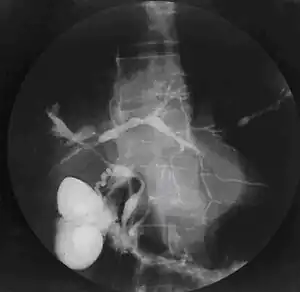

A colangite esclerosante primária (CEP) é uma doença crônica do fígado causada pela inflamação e cicatrização progressivas das vias biliares intra-hepáticas e extra-hepáticas.

O processo inflamatório provoca estreitamentos (estenoses) da via biliar, o que impede a adequada circulação da bile para o intestino. A doença com frequência evolui para cirrose, insuficiência e carcinoma hepáticos, como consequência do potencial inflamatório da bile, que é rica em sais biliares hidrofóbicos e citotóxicos (danosos às células do fígado).